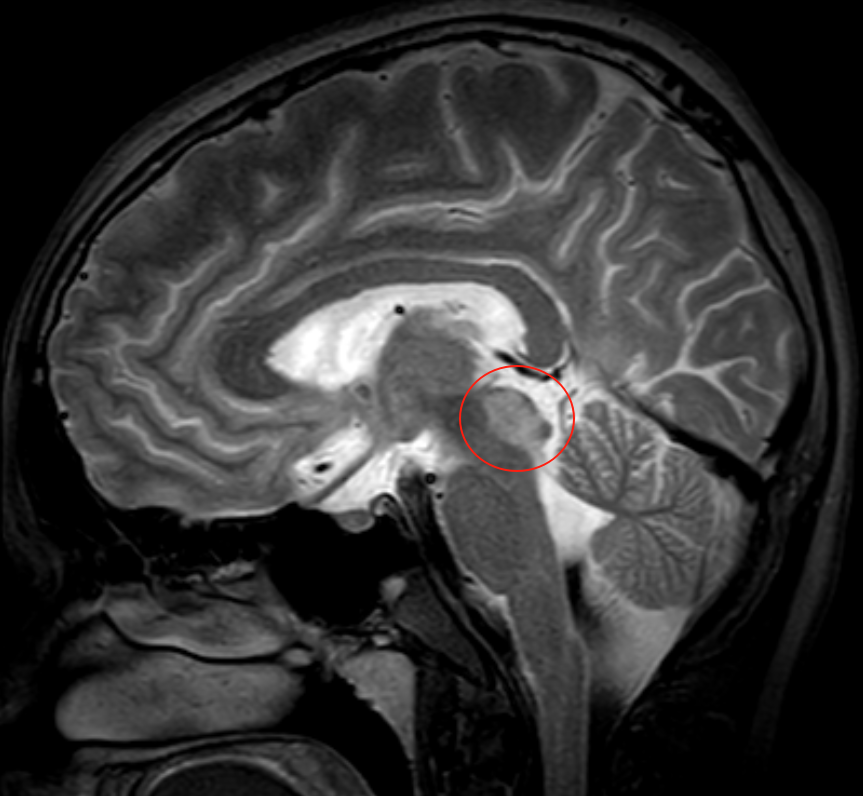

中腦背側(cè)、頂蓋部占位性病變,父母為17歲少年全力托舉

17歲少年2年前因腦積水行分流術(shù),癥狀一度緩解。4個(gè)月前頭痛復(fù)發(fā)伴視物重影,調(diào)整分流壓力無(wú)效。近1月病情進(jìn)展,出現(xiàn)眼球運(yùn)動(dòng)障礙、吞咽困難及嗜睡,影像學(xué)顯示中腦背側(cè)、頂蓋部占位,約19*16*11mm,疑似膠質(zhì)瘤。面對(duì)不斷加重的病情,患者父母帶著希望尋求巴教授的幫助。

影像

巴教授的策略是不同的,”我會(huì)盡量切除腫瘤的絕大部分,這樣我們也能拿到足夠大的標(biāo)本,有助于做出精確的診斷。術(shù)后不到6周,孩子可能回歸校園、正常生活……“